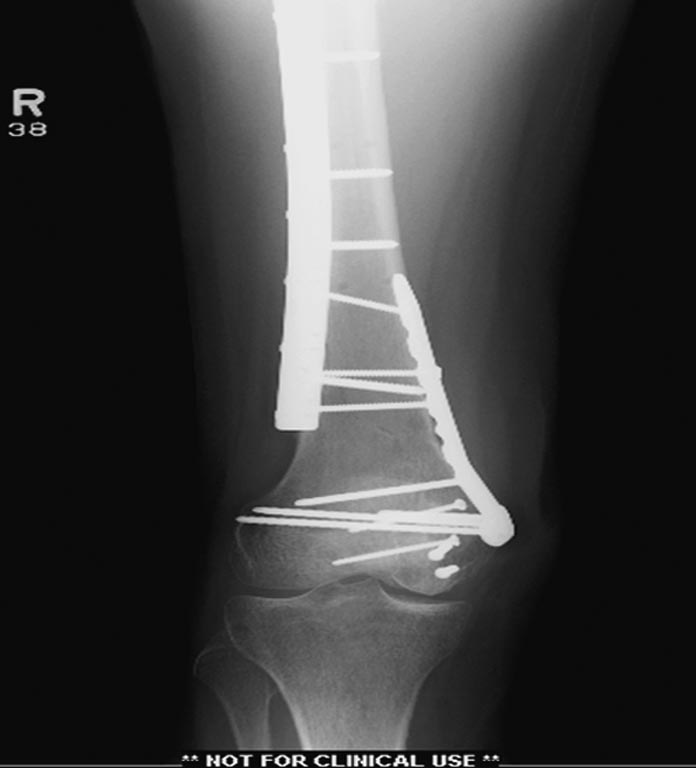

Здесь перечислены ортопедические повреждения: Rt. femoral shaft fracture, Rt femoral head fracture-dislocation, Rt distal femur fracture, Rt. open patella fracture, Rt. talus fracture dislocation, Rt. open humerus fracture, Left 5th metatarsal fracture, Left dislocation 1st TMT.

Раны в области коленного сустава и на плече до сих пор чистые, остаются открытыми. Отсутствует признаки инфекции, решили превратить недостаток в преимущество, т.е. фиксировать через открытые раны пластинами.

На 11й день фиксация плеча также пластиной.